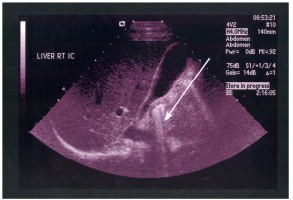

62 附圖中箭號所指的解剖結構為:

(A)左門靜脈主要分支(left main branch) (B)右門靜脈主要分支(right main branch)(C)門靜脈第三節段分支(segment-3 branch) (D)門靜脈第二節段分支(segment-2 branch)